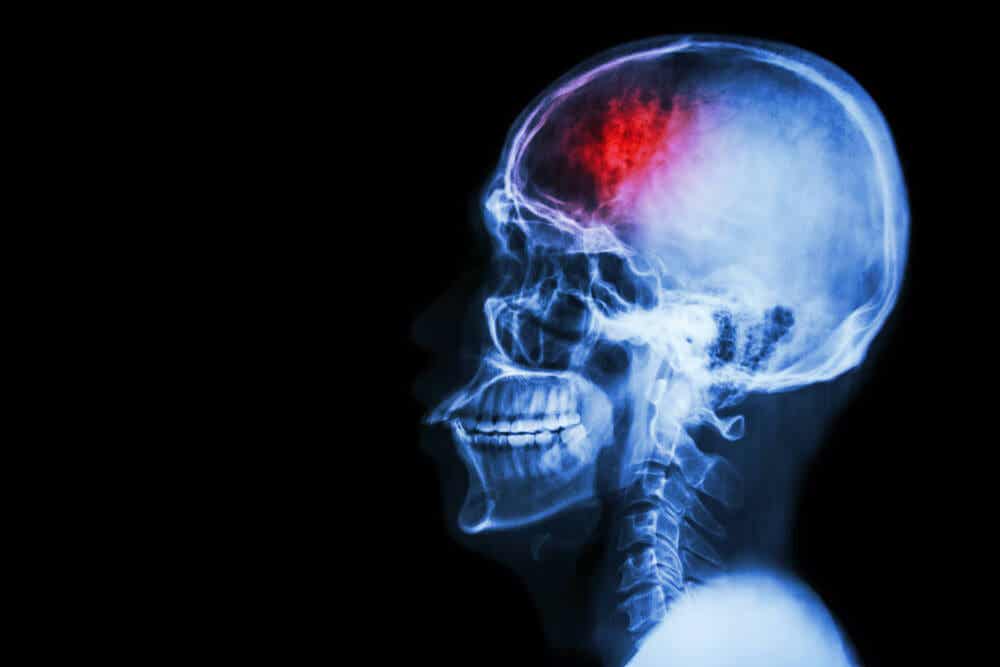

Et intrakranielt hæmatom er ofte livstruende. Og selvom mange af dem kan være små, skal udviklingen overvåges. Det er ikke en tilstand, man må tage let på, og man må heller ikke se det som blot endnu et symptom.

Dette problem udvikler sig, når blod ophobes inde i kranieknoglerne. Placeringen af denne blodansamling er varierende, og det kliniske billede vil ændre sig i henhold til disse positioner.

Et af problemerne med disse hæmatomer er det tryk, de genererer på et følsomt organ, såsom hjernen. Denne øgede spænding skader neuronerne og komplicerer deres funktion.